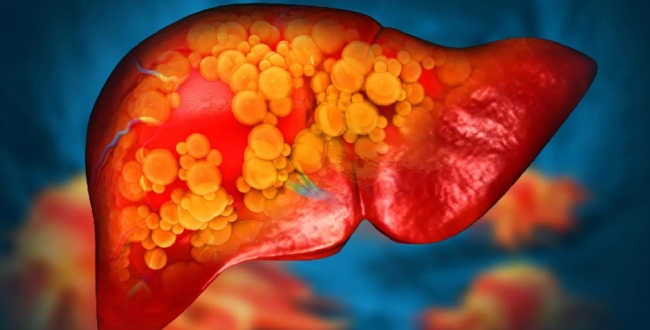

கல்லீரல் அழற்சி (Inflammation)

கல்லீரல் சேதம்

கடுமையான நிலையில் சிரோசிஸ் (கல்லீரல் கடினமாதல்)

கல்லீரல் செயலிழப்பு அபாயம்

இது “மெல்ல மெல்ல கல்லீரலை சிதைக்கும் நிலை” எனக் கருதப்படுகிறது.